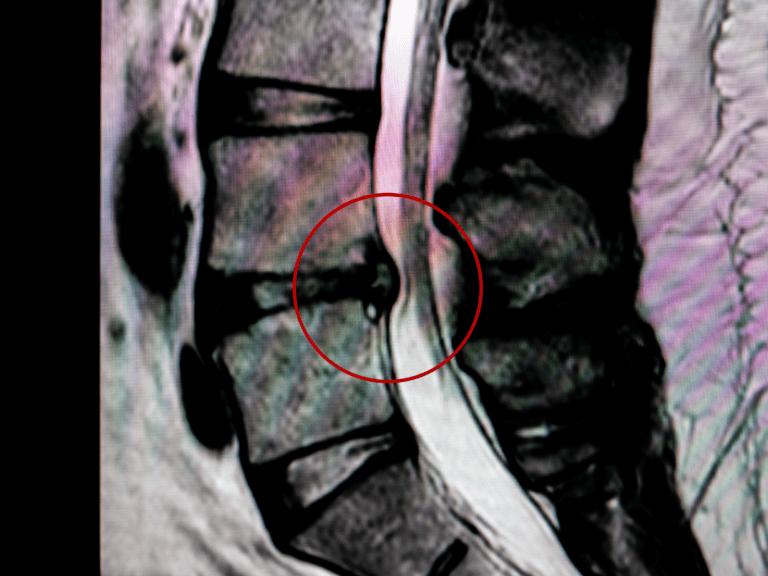

Disc-Related Conditions

Lumbar disc bulges, herniations, or degenerative disc changes may place pressure on nerve roots that form the sciatic nerve, leading to radiating leg pain.